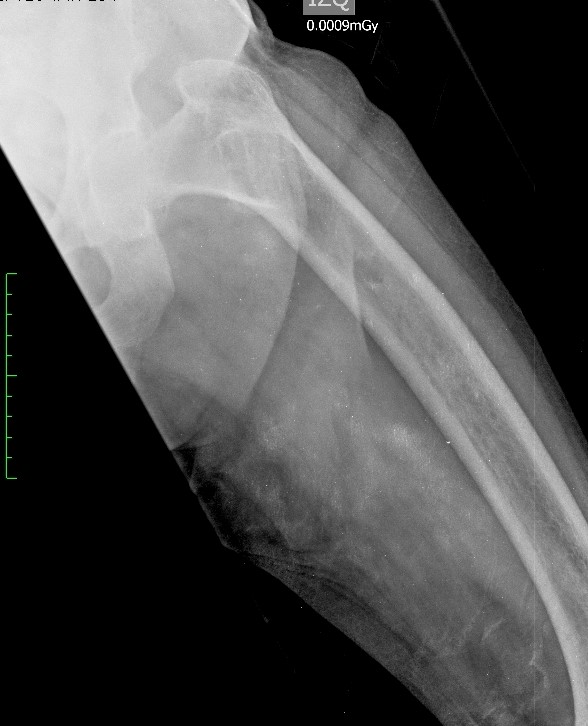

Mujer de 71 años, delgada, con buena funcionalidad previa (Barthel 100/100) y antecedente de osteoporosis, presentó dolor súbito y limitación para la marcha por fractura subcervical de fémur izquierdo (Figura 1), se programó osteosíntesis considerando fractura por fragilidad. Al ampliar estudios se documentó síndrome constitucional de dos meses de evolución, nefrolitiasis, anemia microcítica y lesiones osteolíticas generalizadas (Figura 2). Se consideraron neoplasias de células plasmáticas como el mieloma múltiple y metástasis óseas de neoplasias ocultas, como las ginecológicas. Estudios tomográficos mostraron nódulo pulmonar inespecífico con derrame pleural escaso y nódulo tiroideo de 4 cm (Figura 3), ecografía de tiroides indicó nódulo de alto riesgo y biopsia por trucut reportó adenoma folicular oncocítico.

Radiografía de fémur. Fractura a nivel intertrocantérico izquierdo con ascenso de la diáfisis femoral, cambios por osteoporosis y lesiones osteolíticas. Ampliación con TAC reporta fractura intracapsular de fémur izquierdo, que sugiere proceso atípico.

Figura 1: Radiografía de fémur. Fractura a nivel intertrocantérico izquierdo con ascenso de la diáfisis femoral, cambios por osteoporosis y lesiones osteolíticas. Ampliación con TAC reporta fractura intracapsular de fémur izquierdo, que sugiere proceso atípico.

Fuente: los autores.